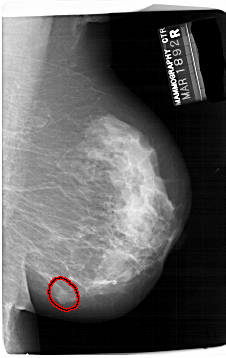

A_1414_1.RIGHT_CC

RIGHT_CC LINES 6871 PIXELS_PER_LINE 4231 BITS_PER_PIXEL 12 RESOLUTION 43.5 OVERLAY

FILE: A_1414_1.RIGHT_CC.OVERLAY

TOTAL_ABNORMALITIES 1

ABNORMALITY 1

LESION_TYPE MASS SHAPE OVAL MARGINS ILL_DEFINED

ASSESSMENT 4

SUBTLETY 3

PATHOLOGY BENIGN

TOTAL_OUTLINES 1

BOUNDARY